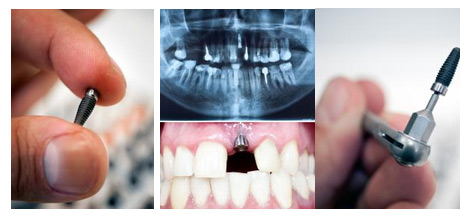

种植牙可以用多久

【种植牙的使用寿命是多长时间】

【种植牙使用寿命是长久性的吗】

康贝佳植牙医生介绍说,种植牙技术已经发展成熟,但种植的牙齿是需要定期检查和维护的,只要后期维护得当,一颗高质量的种植牙能使用几十年,甚至。1965年,第一例种植牙在瑞典诞生,为缺牙者服务超过40年。种植牙寿命主要与以下因素有关: